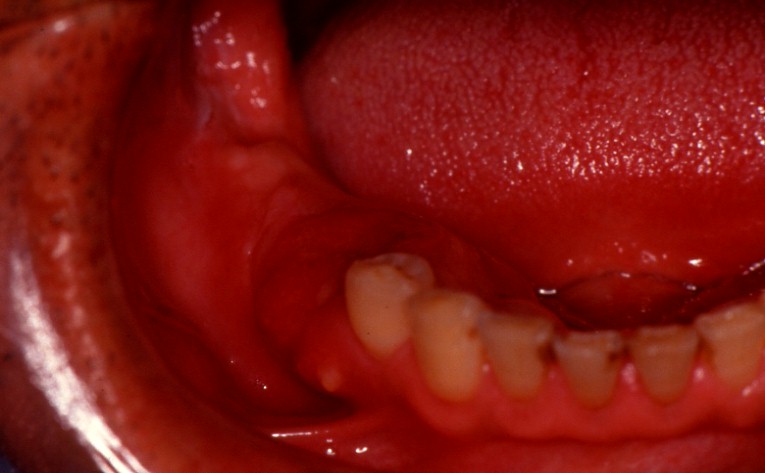

| 歯肉癌 () |

歯肉癌について

口腔癌のうち、舌に次いでこの腫瘍が多い。

好発部位

上下顎別では下顎に多く、発現部位では上下顎とも臼歯部が主である。

早期に顎骨の浸潤破壊をきたしやすい。